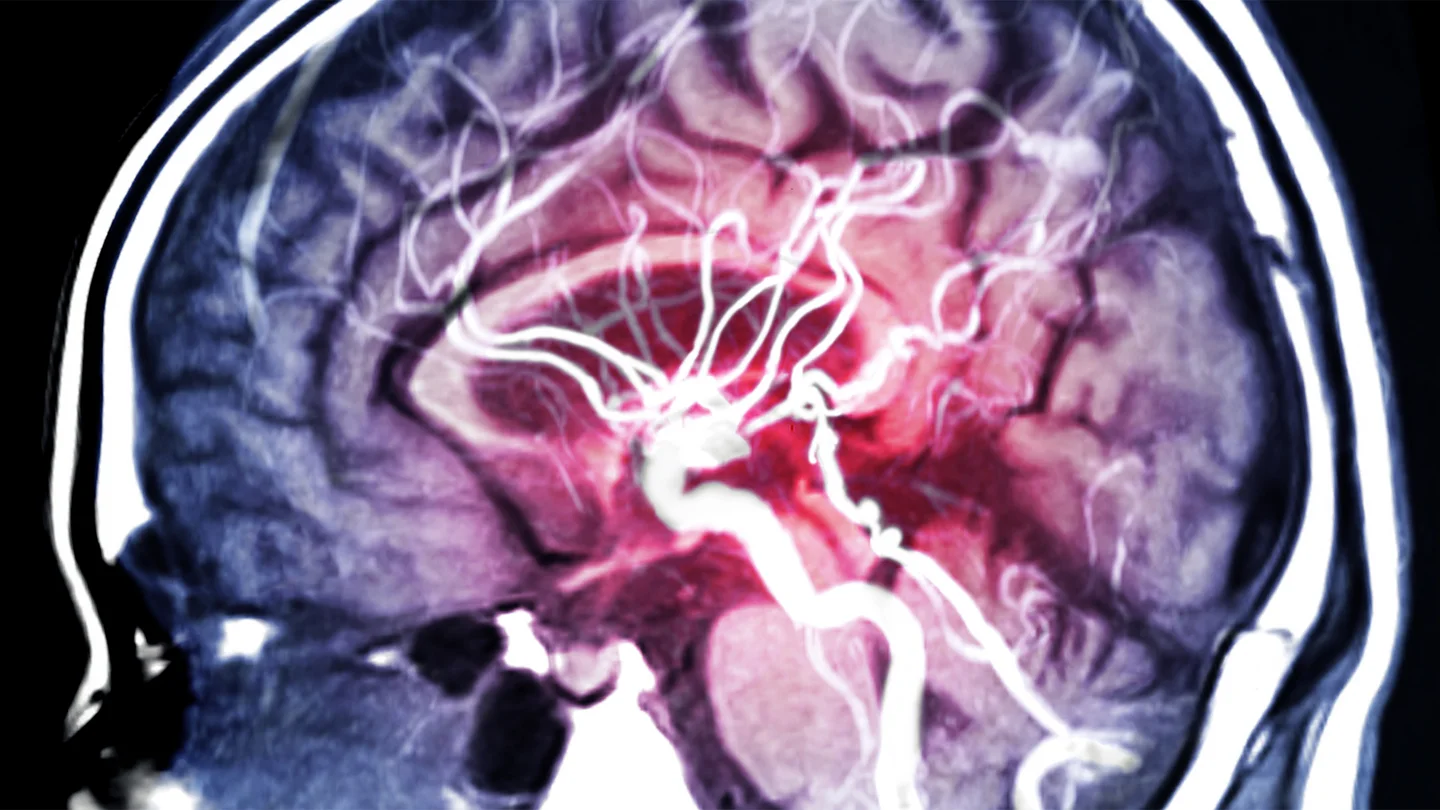

Aneurysms can occur on various arteries, for instance the abdominal aorta. If one of these bulges occurs in an artery in the brain, this is referred to as a brain aneurysm or cerebral aneurysm. This type of aneurysm often develops at branches in the arteries that supply blood to the brain. If a brain aneurysm ruptures, it may cause a life-threatening brain hemorrhage.

If an individual is experiencing frequent headaches or impaired vision, the cause of the symptoms can be identified by a magnetic resonance imaging (MRI) scan or computed tomography (CT) scan.

Aneurysms are particularly easy to detect using a technique known as digital subtraction angiography (DSA), in which an x-ray is taken with and without injecting a contrast medium. The computer can then create an image in which only the blood vessels are visible.